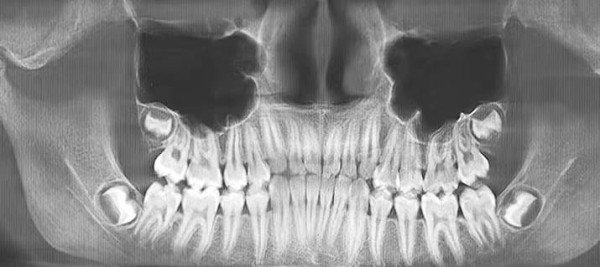

— На ортопантомограмме (см. рис. 2) видно, что зачатки третьих премоляров заложены глубоко, зачатки зубов 1.8 и 2.8 расположены близко к верхнечелюстным пазухам, 4.8 — к нижнечелюстному каналу. Чтобы удалить такие зубы, требуется весьма сложное травматичное вмешательство, как правило, под общим наркозом. При этом показаний для удаления нет, — прокомментировал Яков Тимчук.

Рисунок 2. Ортопантомограмма 15-летнего пациента с глубоко заложенными зачатками 8-х зубов.

— Вот еще один пациент (см. рис. 3) с верхними «восьмерками», залегающими очень близко к верхнечелюстным пазухам, что несет большие риски при удалении. Иногда на удаление направляют пациентов с начинающими прорезываться «восьмерками», при этом показания к удалению отсутствуют, т. е. третьи моляры не препятствуют дистализации (см. рис. 4).

Рисунок 3. Ортопантомограмма 15-летнего пациента с глубоко заложенными зачатками 8-х зубов.